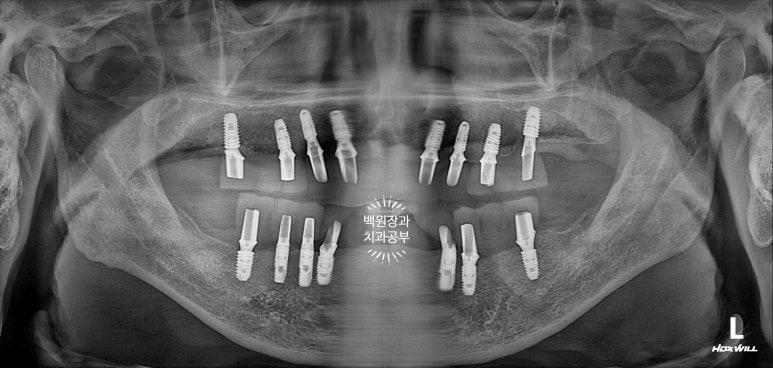

완성 후 치과용 파노라마 사진을 찍었습니다.

저희 치과에서 사용하는 오스템임플란트 네비게이션 시스템을 통해 임플란트 위치를 잘 계획하였고, 그 덕분에 각 치아의 가운데에 잘 맞춰져 임플란트가 위치된 것을 보실 수 있어요.

옛날부터 임플란트 틀니용으로 사용하시던 임플란트 3개는 임플란트 주위염이 조금 있어 약~간 쇠기둥 색깔이 보인다는 단점이 있긴 하지만, 다른 임플란트들은 꽤나 예쁘게 제작이 되었네요.

대부분의 환자분들이 전체임플란트 치료를 받으시면, 위턱 아래턱 각각 3덩어리의 보철물로 제작해드립니다.

즉, 어금니-앞니-어금니 총 3피스의 보철물로 나누어 제작하게 되는데 이는 향후 임플란트 수리도 용이하다는 큰 장점을 갖고 있죠.